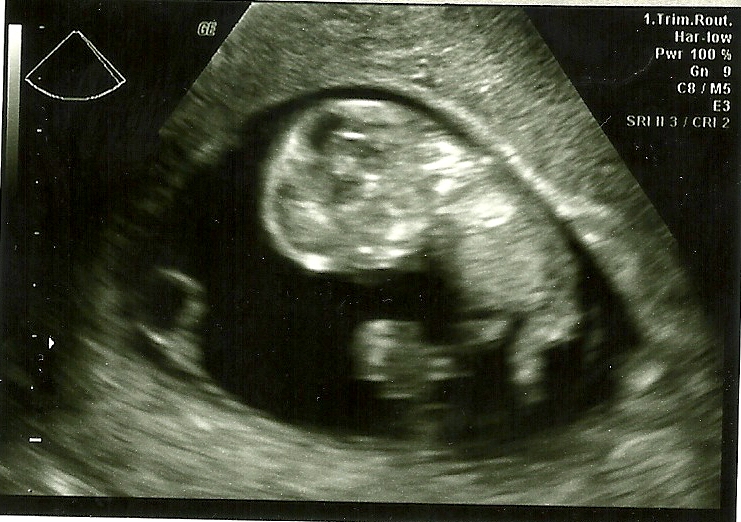

Doyle Baby Two is measuring right on target, and has a beautifully strong heartbeat. For my more visually oriented readers, here is our glorious Bean:

For those not up on their ultrasound reading skills, the black center is where Bean lives. The largest round bit near the top center is a baby head. Following down to the right is baby body then baby leg. Branching toward the center is coiled umbilical cord.

It's so wild that almost exactly 4 weeks ago, our baby looked like a stick attached to a bubble, and now it is pretty much baby-shaped (albeit a bit lacking in birth-ready proportion...). Our medical group has huge monitors attached near the ceiling in their ultrasound rooms so that you can easily see the images in real time. This little one was moving a mile a minute. Legs peddling, arms pumping. Quite impressive for one so tiny (3.43 cm from crown to buns)!

Our baby was feeling mellow and cooperative, so in addition to seeing a beautiful array of skeletal poetry and healthy organ function, we found out that our baby on the way is a boy.

Isn't he just precious ;-) If ultrasound photos are not your 'thing', this is a profile shot. Baby's head is on the left. The 'curlicue' on his forehead is actually the fingers of his right hand. Just above his tummy on the right side, you can see his knee and leg bones. He seemed pretty cramped in there, and I resolved to drink more water, but then I read that babies spend their time curled up like that until around 20 weeks. After that, they start to really stretch (as much as possible). I'm assuming that this has to do with skeletal and muscular development, but assuming is usually unwise... so I have some research to do... but I will also up my water intake!